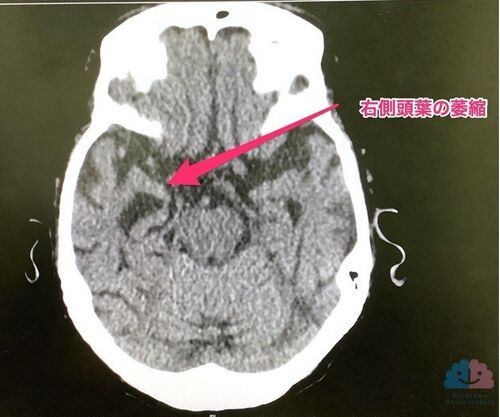

【症例報告】トラゾドン(レスリン・デジレル)で落ちついた96歳女性。

今回紹介する超高齢女性は、なかなかに手強い人だった。 手応えのあったウインタミンが副作用で使えなくなったのは痛かったが、最終的には、初期から入れていたトラゾドンが、睡眠のみならず全体を上手くまとめてくれた。